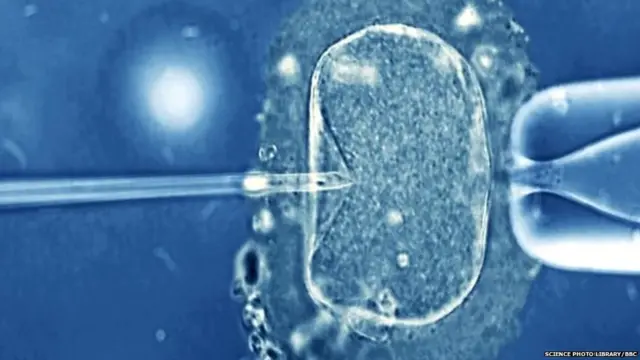

ਤਸਵੀਰ ਸਰੋਤ, Science Photo Library/bbc

ਕੋਈ ਏਅਰਲਾਈਨ ਲਿਕਵਡ ਨਾਈਟਰੋਜਨ ਦੀ ਬੋਤਲ(ਜਿਸ 'ਚ ਭਰੂਣ ਨੂੰ ਰੱਖਿਆ ਗਿਆ ਸੀ) ਲੈ ਕੇ ਜਾਣ ਨੂੰ ਤਿਆਰ ਨਹੀਂ ਨਹੀਂ ਸੀ। ਇਸ ਲਈ ਉਸ ਨੂੰ ਕਾਰ ਰਾਹੀਂ ਲਾਓਸ ਲਿਆਂਦਾ ਗਿਆ।

ਲਾਓਸ ਵਿੱਚ ਸਰੋਗੇਟ ਮਾਂ ਦੀ ਕੁੱਖ ਵਿੱਚ ਇਸ ਭਰੂਣ ਨੂੰ ਪਲਾਂਟ ਕਰ ਦਿੱਤਾ ਗਿਆ ਅਤੇ ਦਸੰਬਰ 2017 ਵਿੱਚ ਬੱਚਾ ਪੈਦਾ ਹੋਇਆ।